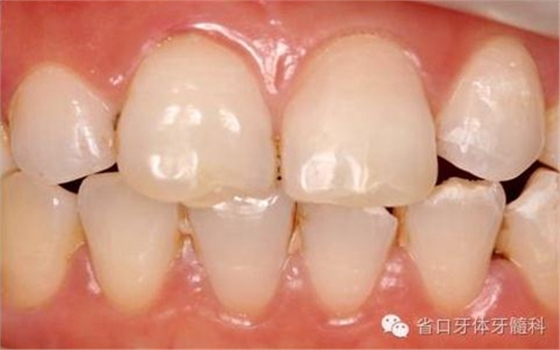

圖2. 術前口內(nèi)照片,21/冠折。

圖16. 術后口內(nèi)照

圖18. 術后23天隨訪的口內(nèi)照片